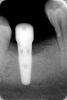

Dagaeva Опубликовано 5 июня, 2012 Автор Поделиться Опубликовано 5 июня, 2012 В марте. До чистки испланта и кости... Ссылка на комментарий

kriokov Опубликовано 5 июня, 2012 Поделиться Опубликовано 5 июня, 2012 Ваше слово, как самый страшный приговор( я очень этого боюсь. А что Вы увидели на этом снимке, что так безкомпромисно "удаляйте". Мне нужно понимать , т.к. моя клиника и врачи в ней против...говорят можно спасти. Что у меня там - инфекция, аллергия, травма...????Заранее спасибо.мнение, не истина в последней инстанции. На снимке видно убыль кости с оголением третьего витка резьбы имплантата с одной из его поверхностей. Дождитесь ответа других врачей форума, обсудите проблему в клинике, примите решение. Ссылка на комментарий